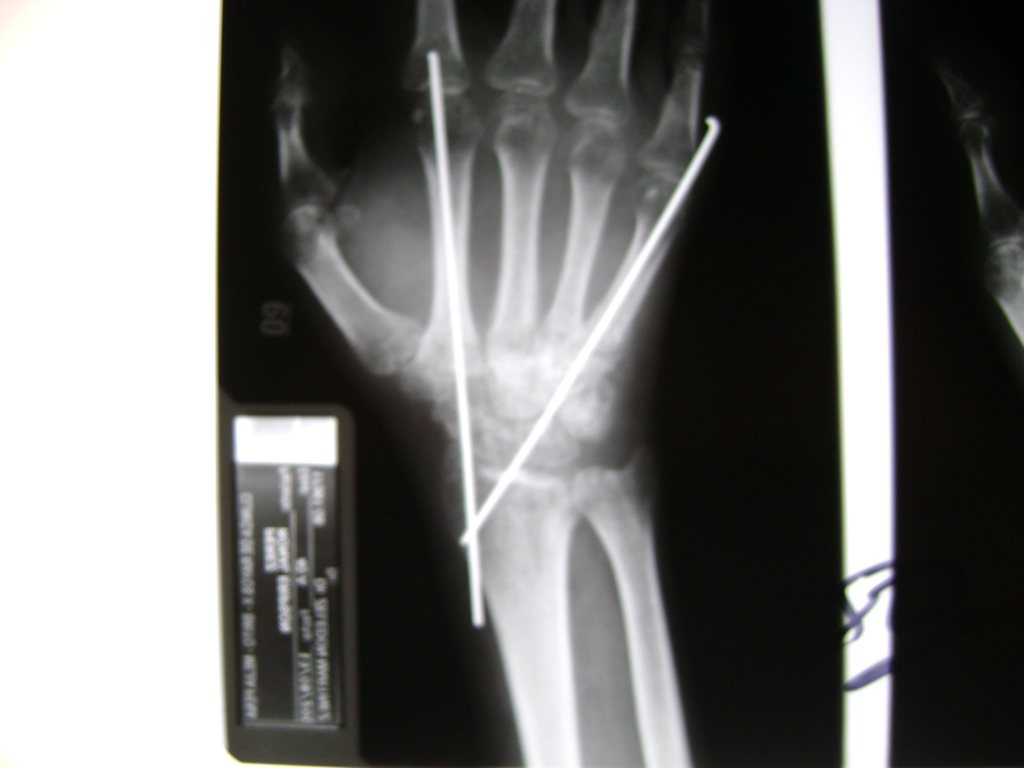

Cirugías de Codos - Cirugías de Muñecas y Manos

Los procedimientos más comunes en cirugía de la mano son aquellos destinados a reparar traumatismos, incluyendo lesiones de tendones, nervios, vasos sanguíneos, y articulaciones; huesos fracturados; y quemaduras, cortes, y otros daños de la piel.